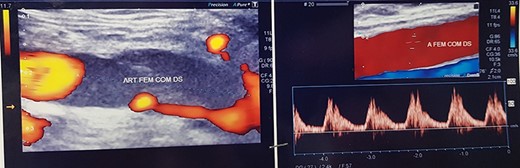

Duplex ultrasound examination (DUS, Fig. 1) showed a segmental sub-occlusive hypoechoic stenosis of the anterior wall of the right CFA.